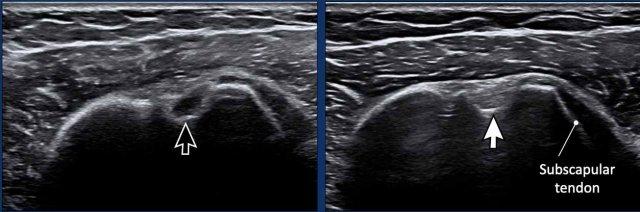

Tính dị hướng là một artefact xảy ra khi chùm tia siêu âm không vuông góc với gân cơ nhị đầu dài (LHB). Sự lệch trục này dẫn đến giảm phản xạ sóng âm, gây mất độ phân giải và làm cho cấu trúc có hình ảnh tối, giảm âm (mũi tên đen). Trong một số trường hợp, điều này có thể tạo ra ấn tượng rằng gân LHB bị trật ra khỏi rãnh liên củ.

Để khắc phục hiện tượng dị hướng, hãy điều chỉnh lại vị trí đầu dò sao cho chùm siêu âm vuông góc với gân. Khi đó, gân cơ nhị đầu dài (LHB) sẽ lấy lại hình ảnh đặc trưng tăng âm, dạng sợi (mũi tên trắng).

Cần lưu ý rằng hiện tượng dị hướng cũng có thể ảnh hưởng đến các cấu trúc khác, chẳng hạn như gân cơ dưới vai trong hình ảnh này, tương tự cũng xuất hiện giảm âm do hiện tượng nhiễu ảnh này.